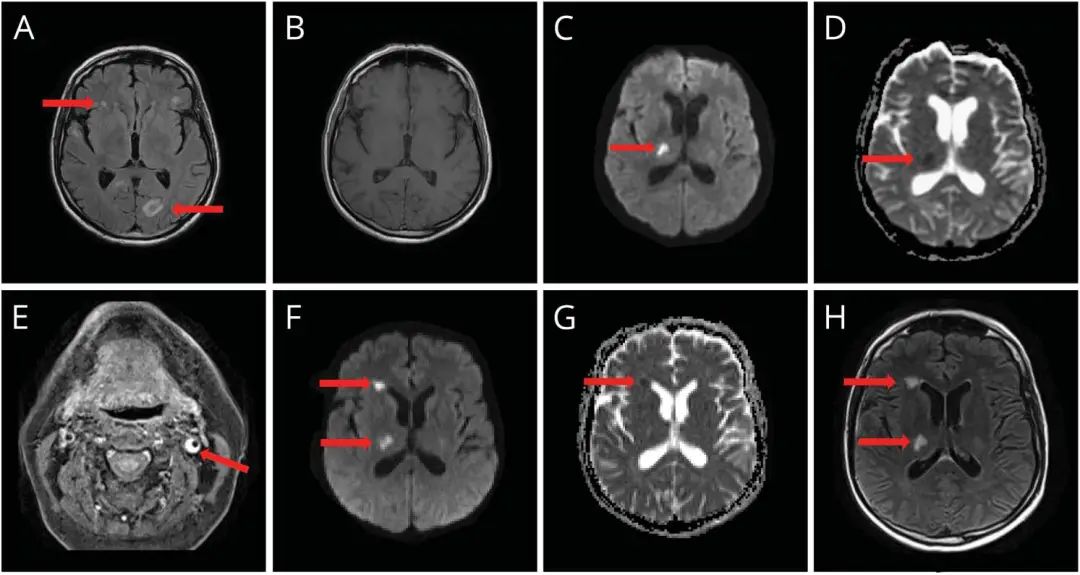

患者为65岁农民,因“不适、头痛、发烧和易怒2周”就诊。患者随后出现意识混乱及右侧第四颅神经麻痹。腰穿考虑为淋巴细胞性脑膜炎。CSF淋巴细胞为405个/μL,单核细胞90%,蛋白升高189 mg/dL(15-45 mg/dL),血清与CSF的葡萄糖比率正常。CSF VZV PCR提示阳性。患者否认有皮疹,HIV阴性,除年龄外未发现任何免疫抑制的因素。脑部MRI显示额叶和枕叶白质改变,无增强,也无弥散受限(图1,A和B)。患者接受了20天静脉注射阿昔洛韦治疗,临床症状得到改善。

一个月后,患者醒来时发现部分左偏瘫和偏身感觉障碍。复查头颅MRI显示右侧丘脑后外侧急性梗死(图1,C和D)与水痘血管病相符。第二次腰穿显示淋巴细胞增多,白细胞增至81个/μL(99%单核),蛋白进一步升高至206 mg/dL,无红细胞,VZV PCR阳性。

CT血管造影显示右侧大脑中脑动脉M2段血栓形成,左颈内动脉(ICA)壁增厚,从起始部到颅底狭窄,与颈动脉夹层一致,但无相关症状。1周后 T1脂抑制MRI证实了夹层(图1,E),而头颅MRI没有显示相应的梗塞,但确实显示了另外的无症状性右额梗死(图1,F和G)。

图1 患者相关影像结果。 (A)最初头颅MRI FLAIR序列显示额叶和左枕角深部白质异常; (B)增强序列未见明显强化; (C和D)DWI和ADC序列可见右侧丘脑急性梗死; (E)颈部T1脂肪饱和轴向MRI显示左颈内动脉壁同心高信号增厚,管腔口径减小,与夹层一致(红色箭头); (F和G)间隔随访的DWI(B1000)和ADC图,显示右额叶明显弥散受限,右侧丘脑稍弱弥散受限; (H)FLAIR序列可见相应改变。